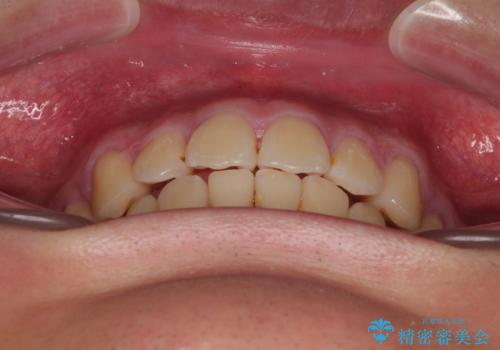

- 全顎的なデコボコを気にして来院された患者様です。

特に前歯のデコボコが顕著であり、上下左右第一小臼歯の4本を抜歯し、ワイヤー装置を使用して咬み合わせ高さを改善しながら、歯列を整えて行くこととしました。